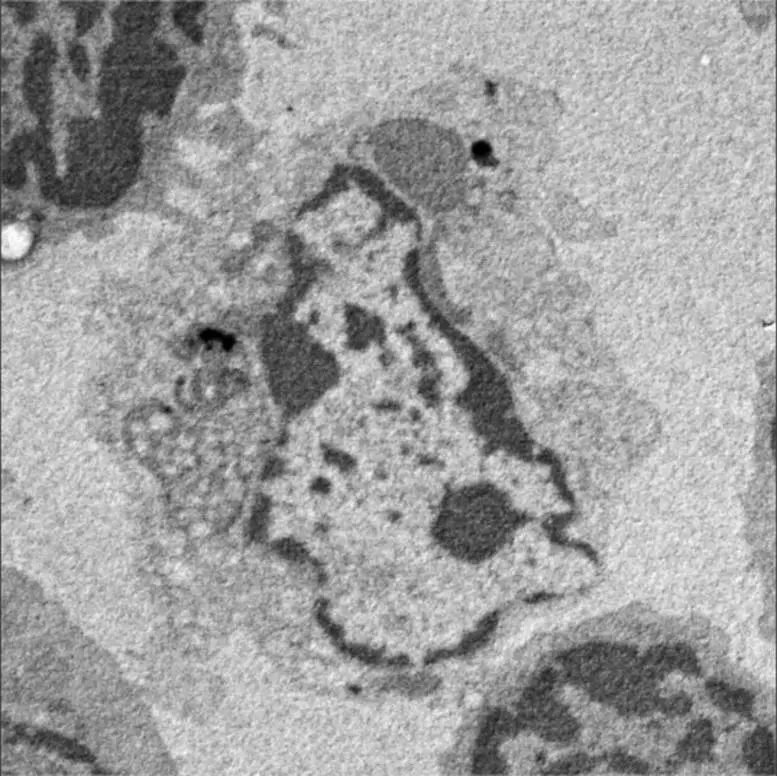

他们的研究结果发表在《美国国家科学院院刊》(PNAS)上,明确指出树突状细胞是杀死缺乏 CD47 的 T 细胞的细胞。这不仅首次揭示了CD47缺陷T细胞消失背后的机制,还揭示了树突状细胞完全意想不到的能力。斋藤说:"这一结果是完全新颖的,因为人们认为CD47缺陷细胞会被一种叫做'巨噬细胞'的免疫细胞吞噬,而且树突状细胞从来不会诱导其他免疫细胞的细胞死亡。因此,研究小组发现了一种人体识别缺失自我细胞的全新方法,即缺乏 CD47 的细胞直接被树突状细胞杀死。"